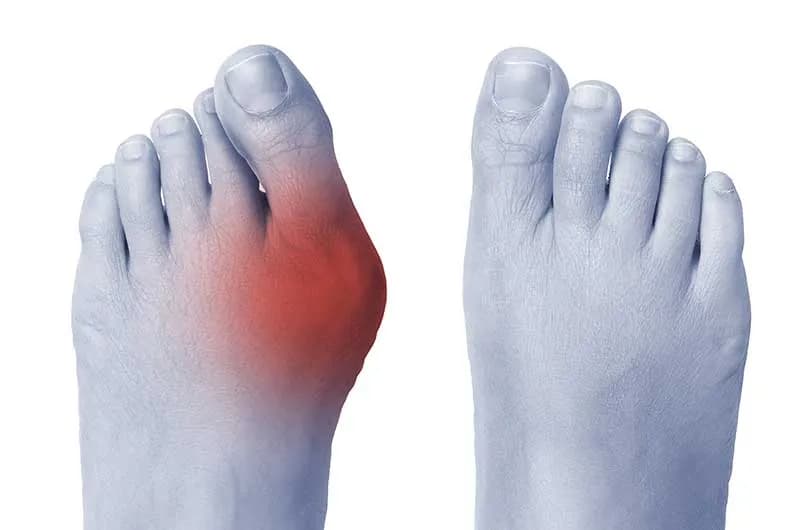

- Stan zapalny: W okolicy stawu, u podstawy dużego palca, często pojawia się zaczerwienienie, obrzęk i miejscowe podwyższenie temperatury skóry. To znak, że organizm walczy z podrażnieniem.

- Deformacja wizualna: Najbardziej oczywistym objawem jest widoczne wygięcie palucha w kierunku pozostałych palców oraz charakterystyczny, kostny guzek po wewnętrznej stronie stopy.

Choć haluks to deformacja dużego palca, ból nie zawsze ogranicza się tylko do niego. Zazwyczaj jednak najbardziej dotkliwe dolegliwości lokalizują się w okolicy stawu u podstawy dużego palca, po wewnętrznej stronie stopy tam, gdzie tworzy się charakterystyczny guzek. To właśnie ten obszar jest najbardziej narażony na ucisk, tarcie i stan zapalny. W miarę postępu deformacji ból może jednak promieniować na całe przodostopie, obejmując sąsiednie palce i podeszwy stopy. Wynika to z nieprawidłowego rozłożenia ciężaru i przeciążenia innych struktur stopy, które próbują kompensować dysfunkcję palucha.